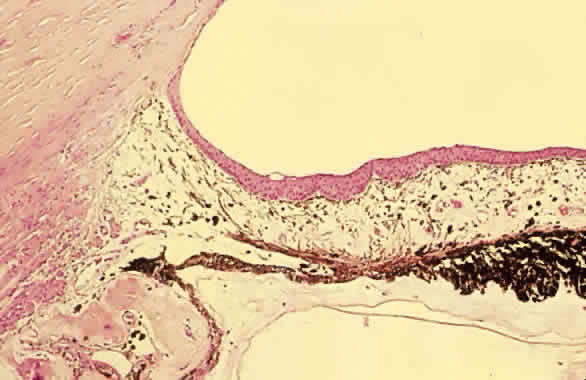

Perforating injuries create a pathway for epithelial and fibrous connective tissue to grow into the eye.31 Membranes, often with scalloped edges, may proliferate across anterior chamber structures including the iris and corneal endothelium (Fig. 6). These membranes cover the trabecular meshwork and lead to reduced outflow. The membranes may be identified by argon laser treatment over affected portions of the iris. The laser creates white, rather than brown, spots.

Fig. 6. Epithelial ingrowth. An epithelial membrane covers the anterior iris and the anterior chamber angle recess. (Courtesy of Ralph C. Eagle, Jr.)